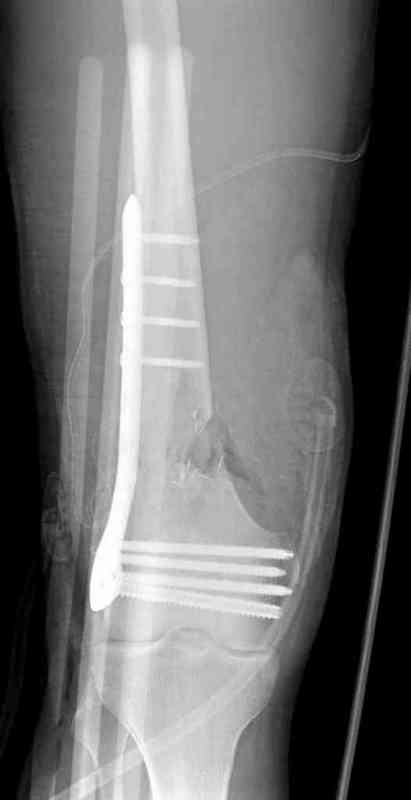

Вчера утром поступил больной с огнестрельной раной, осмотрен сосудистым специалистом, сделана ангиограмма (снимки) Во время операции при вскрытии обнаружили кровотечение, рану забили салфетками, установили пластину locking DePuy.

Из-за возрастающего давления в компартменте сделана фасциотомия и вызванный сосудистый хирург ушил разрыв вены на уровне перелома. Все раны оставлены открытими, в пятницу закроем.